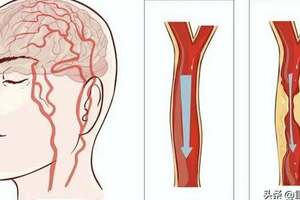

據統計,有超過60多種疾病與濕氣有關。如肥胖、水腫、腹脹、濕疹、皮炎、痤瘡、泌尿系統感染、女性白帶增多瘙癢等。

最嚴重的是:濕氣可能引起頑固性肥胖,這種肥胖引發一系列的疾病,如高血壓,高血脂,甚至會引發惡性腫瘤,身上的腫瘤切了又長,長了又切。因此,去除體內濕氣,刻不容緩!